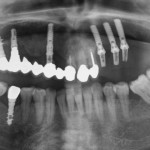

Riabilitazione parziale del mascellare edentulo posteriore con applicazione del principio All-on-4

La riabilitazione dell’edentulia parziale nel mascellare posteriore rappresenta una sfida a causa della densità ossea inferiore e dell’insufficiente quantità di osso dovuta alla presenza...